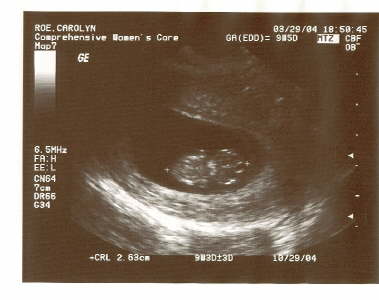

Baby Shot 1